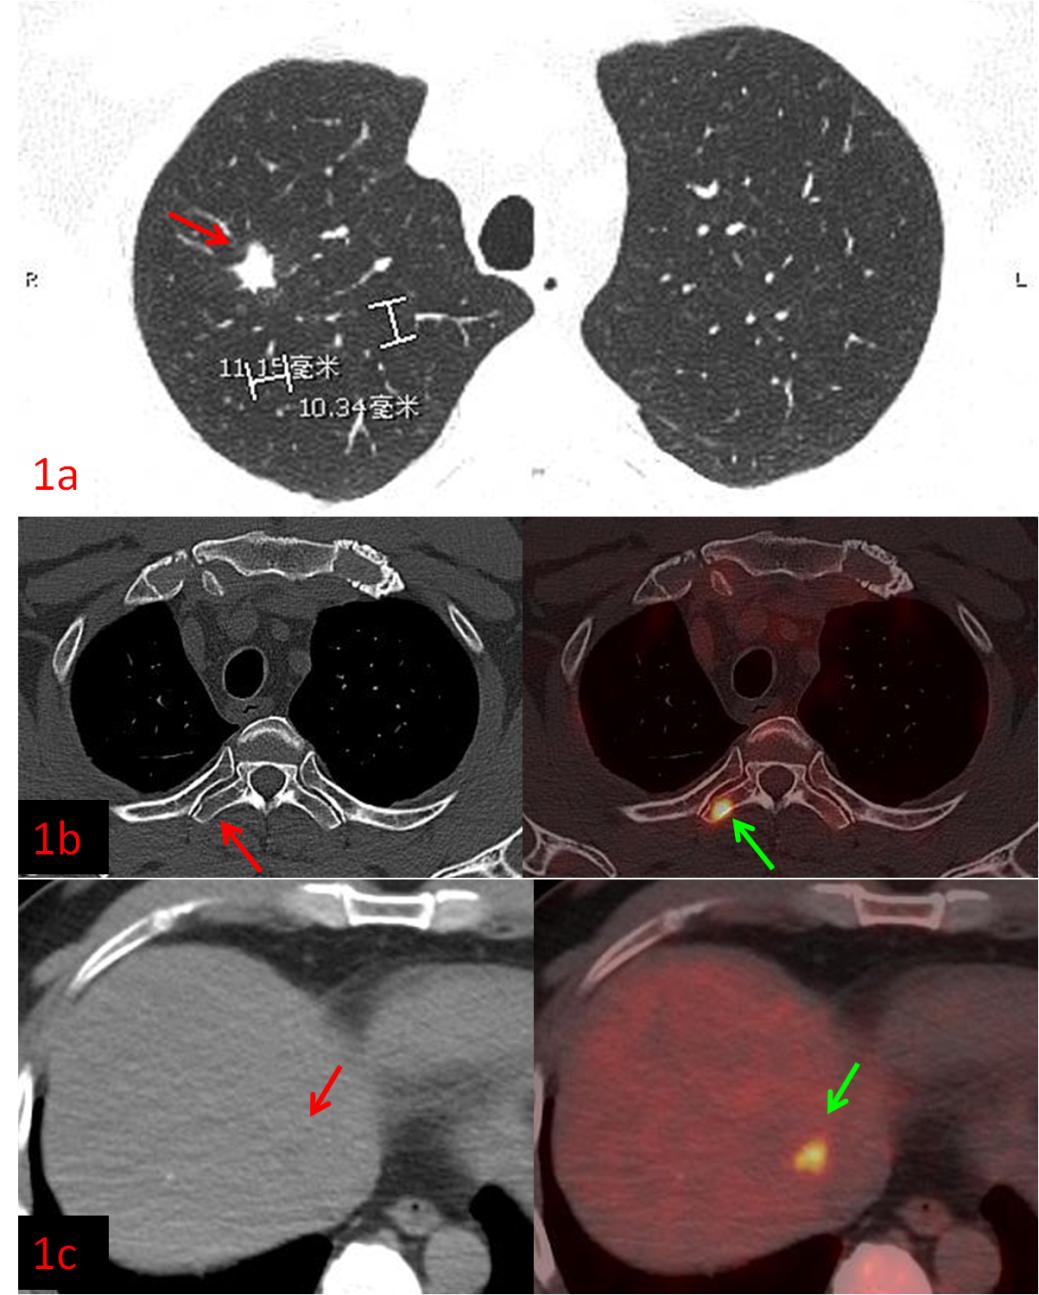

例1:中年男性,CT發(fā)現(xiàn)右肺上葉結(jié)節(jié),1.1cm×1.0cm,余未見異常,這時候患者初步分期應(yīng)該是ⅠA期,屬于早期肺癌,可以行根治性手術(shù)。而PET/CT檢查示:肝臟、多發(fā)骨骼轉(zhuǎn)移,這時候分期直接跳到ⅣB期,屬于晚期肺癌,不適合手術(shù),可以根據(jù)病理、基因檢測結(jié)果選擇合適的藥物治療或聯(lián)合治療方案,避免了無效的手術(shù)創(chuàng)傷。病理:浸潤性腺癌。